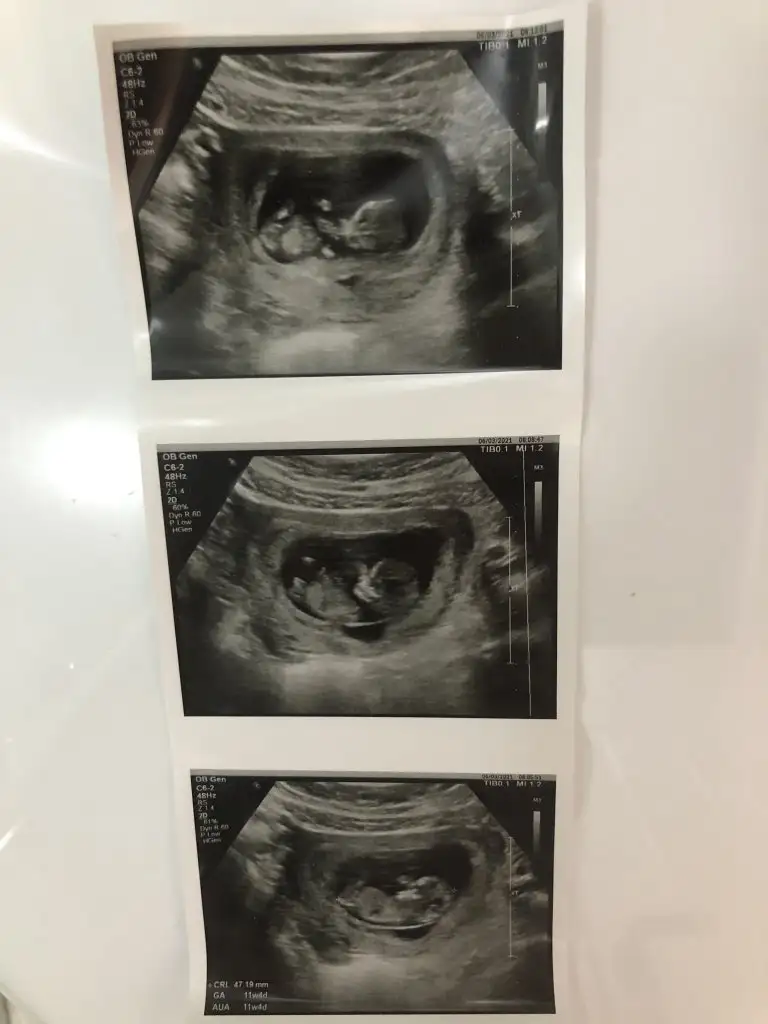

Heyecanla cevabını bekliyoruzMerhabaIkra meyra benim de bebeğimin fotoğrafı bu şekilde. 11+4 deyiz :) doktor göremedim ama acaba nubunu görebilir misiniz?

Erkek sanki 12-13 olursa paylaşınmerhabaIkra meyra 11+1 karından ultrasyon fotografım cinsiyet hakkında bir yorumda bulunursan çok sevinirim

Erkek sanki 12-13 olursa paylaşınMerhabaIkra meyra benim de bebeğimin fotoğrafı bu şekilde. 11+4 deyiz :) doktor göremedim ama acaba nubunu görebilir misiniz?

Kız gibi sanki emin olamadım13 haftalık cinsiyet tahmini yapabilir misiniz?Ikra meyra

USG yarım almis Dr11+3 bebeğimin ultrason görüntüsüIkra meyra tahmin edebilir misiniz